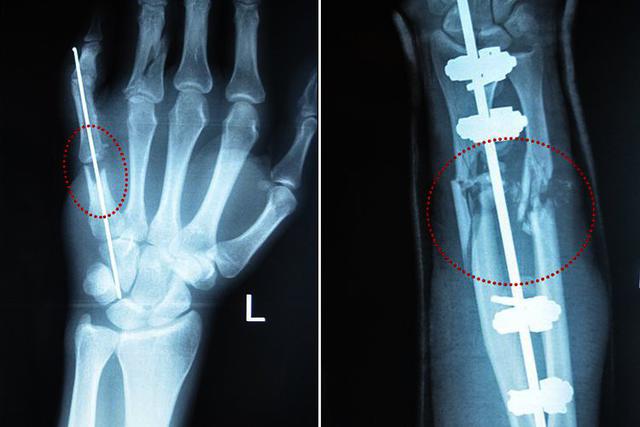

"Євген приєднався до проекту відносно недавно. У молодого розвідника важко пошкоджені обидві руки і нога. Євген пройшов гарячі точки фронту буквально на вістрі атаки. Під час чергового бою, де противником була морська піхота окупанта, зазнав значних поранень. Навіть важко поранений чоловік намагався продовжити бій, і побратими силою вивели його з-під обстрілу. На момент початку лікування Євген мав пошкоджені зв'язки правого коліна, звичний вивих правого плеча, розбите праве передпліччя, були роздроблені кістки лівої кисті. У державних лікарнях ішлося про ампутацію пальців і фіксування переломів пластинами, і чоловік звернувся до проекту "Біотех-реабілітація поранених".